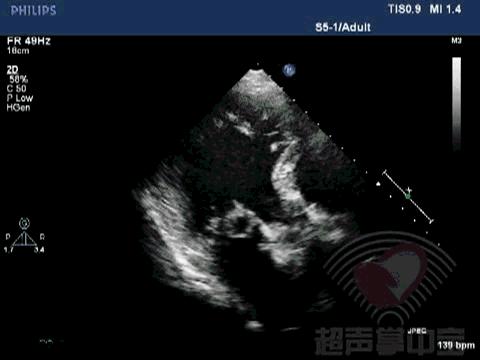

二尖瓣充血性囊肿,二尖瓣血性囊肿是什么意思 图1:心尖四腔心切面显示二尖瓣前叶增厚,前叶左房面可见一囊袋状物附着,大小2.01×2.17cm,囊壁完整,其内透声良好

二尖瓣充血性囊肿,二尖瓣血性囊肿是什么意思 动态图2:四腔心切面显示该囊状物质软,有形变,二尖瓣开放正常

二尖瓣充血性囊肿,二尖瓣血性囊肿是什么意思 动态图3:左室长轴切面观察该囊状物质软,有形变,随二尖瓣运动而摆动